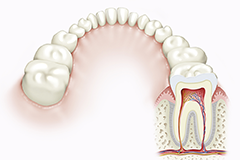

恒赐Tattoo成员演绎与纹身文化结合的DEALER STREAK恒赐Tattoo成员演绎与纹身文化结合的DEALER STREAK植牙,就是将人工牙根植入牙槽...